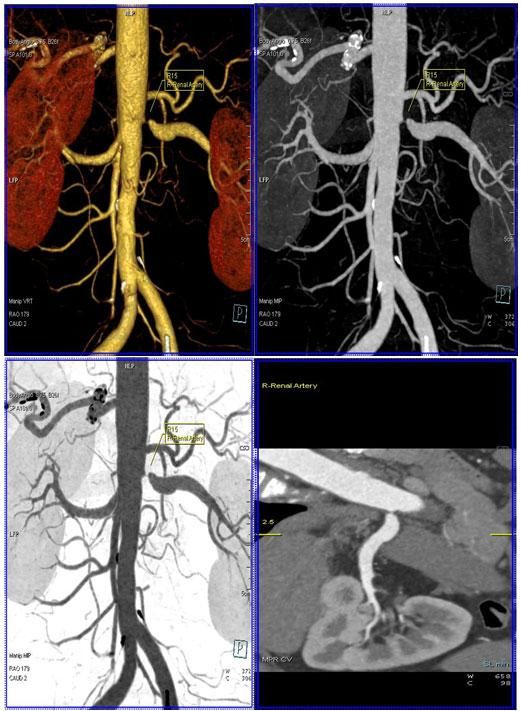

二、多層螺旋CT頭頸部及體部血管成像技術:

該機掃描覆蓋範圍廣、時間短,多種後處理分析軟件能顯示各血管細小分支,可以清晰顯示動脈瘤、動脈夾層、血管畸形、血管狹窄及動脈粥樣硬化斑塊等,适用于頭頸部血管成像、肺動脈成像、胸腹部血管成像及四肢血管成像。

4、腎動脈血管成像(腎動脈狹窄):